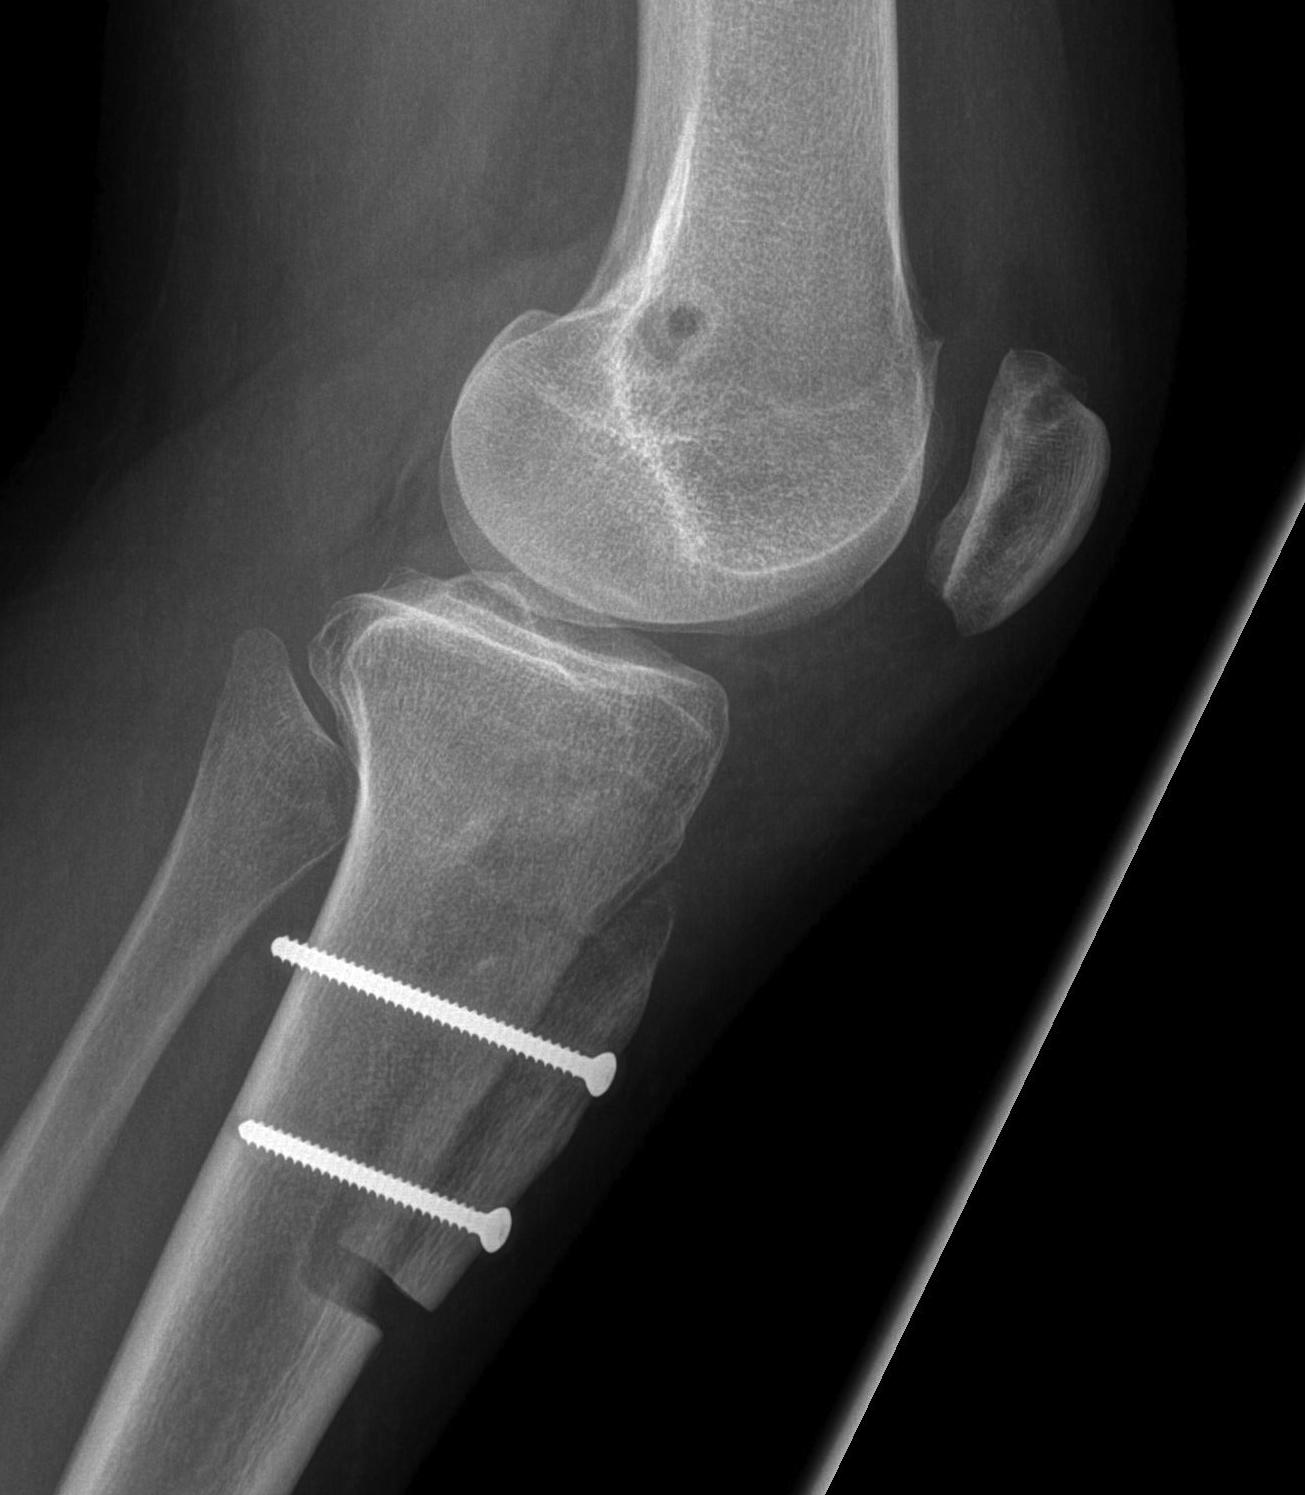

2. Perform TTT (if TTTG > 20)

- incision over TTT

- medialise at least 1 cm

- ensure some element of Fulkerson / anteriorise

- can distalise if patella alta

- secure with screws (2 x small fragment usually sufficient)

- reassess stability

3. MPFL reconstruction (with TTT, or if TTTG < 20)

- acts as checkrein to lateral displacement

- usually harvest hamstring autograft

- medial incision

- beware overtightening (will give pain) / patella fracture (drill holes in patella)

- reassess for stability